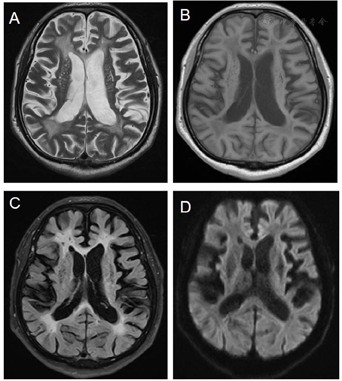

全血细胞计数、肝肾功能、血糖、心肌酶、血脂、梅毒、艾滋、尿酸、血电解质和甲状腺功能检查均正常。颅脑磁共振及血管成像示双侧额顶叶深部白质、放射冠区多发缺血、腔梗灶,脑小血管疾病,Fazekas 3级,符合脑动脉硬化改变(图1)。智能精神测定评分示汉密尔顿焦虑量表(Hamilton anxiety scale,HAMA)为14分,明确有焦虑症状;汉密尔顿抑郁量表(Hamilton depression scale,HAMD)为18分,有轻微抑郁症状;简易精神状态检查(mini mental status examination,MMSE)为13分,有痴呆表现;蒙特利尔认知评估量表(Montreal cognitive assessment,MoCA)为7分,有明显认知损害。Neuro 11为25分(图2)。高密度脑电图提示:θ、δ波段在左侧枕区、中央区和颞区脑连接增多,脑连接示前额叶连接增强,符合血管性认知功能障碍的临床特征(图3)。